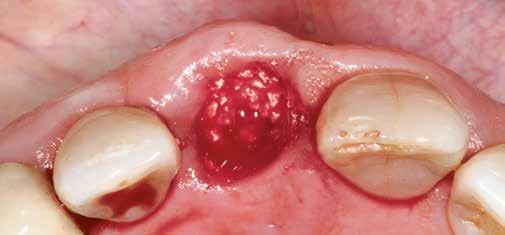

1. ábra: Műtét előtti fogászati panorámafelvétel, amelyen a hiányzó felső állcsont jobb első premolárisát és a szabad véggel rendelkező hidat láthatjuk. — 2. ábra: Az implantátum méreteinek megtervezése CBCT-vel. 3. ábra: Bukkális lágyrészdefektus. — 4. ábra: A biológiai szélesség értékelése a vertikális lágyszövetvastagság alapján. 5. ábra: Palatinális „tekercslebeny” – Palatal roll flap. — 6. ábra: Bredent medical copaSKY 4x10 implantátumbeültetés. 7. ábra: Szubkresztális implantátumbeültetés a várható biológiai szélességnek megfelelően.

(2. ábra). A lágyszövetek értékelése Seibert szerinti I. osztályú csontdefektust állapított meg (3. ábra), ezért a beavatkozáskor palatinális „tekercslebenyt” preparáltunk (palatal roll flap), és implantációt végeztünk, hogy kompenzálni tudjuk a bukkális lágyszövet-behúzódást. Megmértük a vertikális lágyszövetvastagságot, és úgy terveztük, hogy a szubkresztális implantátum beültetése összhangban legyen a biológiai szélesség kialakulásával a transzgingivális gyógyulási periódus alatt (4. ábra)

Az eljárást helyi érzéstelenítés mellett végeztük (4%-os articaine-hidroklorid 1:100 000 adrenalinnal). Papillakímélő, U alakú palatális bemetszést végeztünk, teljes vastagságú nyálkahártyalebeny preparálás történt, a lebenyt bukkálisan feltekertük (5. ábra). A lebeny bukkálisan feltekert részén de-epitelizációt végeztük el, amellyel kompenzálni tudtuk a bukkális lágyszöveti defektust. Szakaszos előfúrást végeztünk, és a bredent copaSKY 4x10 implantátumot 30 Ncm behajtási nyomatékkal helyeztük be (6. ábra). Az implantátumot 1 mm-re szubkresztálisan helyeztük be, hogy később szélesebb emergenciaprofilt tudjunk kialakítani (7. ábra). Az egyedi ínyformázó úgy készült, hogy kompozitot vittünk fel a titánbázisra, és így formáztuk a lágyszöveteket a transzgingivális gyógyulási fázis során (8. ábra). Az egyéni ínyformázó tulipán formájú, hogy kialakítsa a kívánt emergenciaprofilt. A lágyszövetet feszülésmentesen zártuk #6/0 nem felszívódó, monofil fonallal (Optilene, B. Braun Deutschland; 9. a–b. ábra). Posztoperatív röntgenfelvétel készült, ami alapján az implantátum a szomszédos fogakkal párhuzamos elhelyezést mutatott (10. ábra). Posztoperatív utasításokat adtunk a páciensnek a műtéti terület körüli szájhigiénia fenntartása érdekében. A beavatkozást követő egy héttel a varratokat eltávolítottuk, és a kezelt terület kielégítő gyógyulást mutatott (11. ábra). A 4 hónap utáni késleltetett terhelést a páciens kívánsága szerint terveztük.